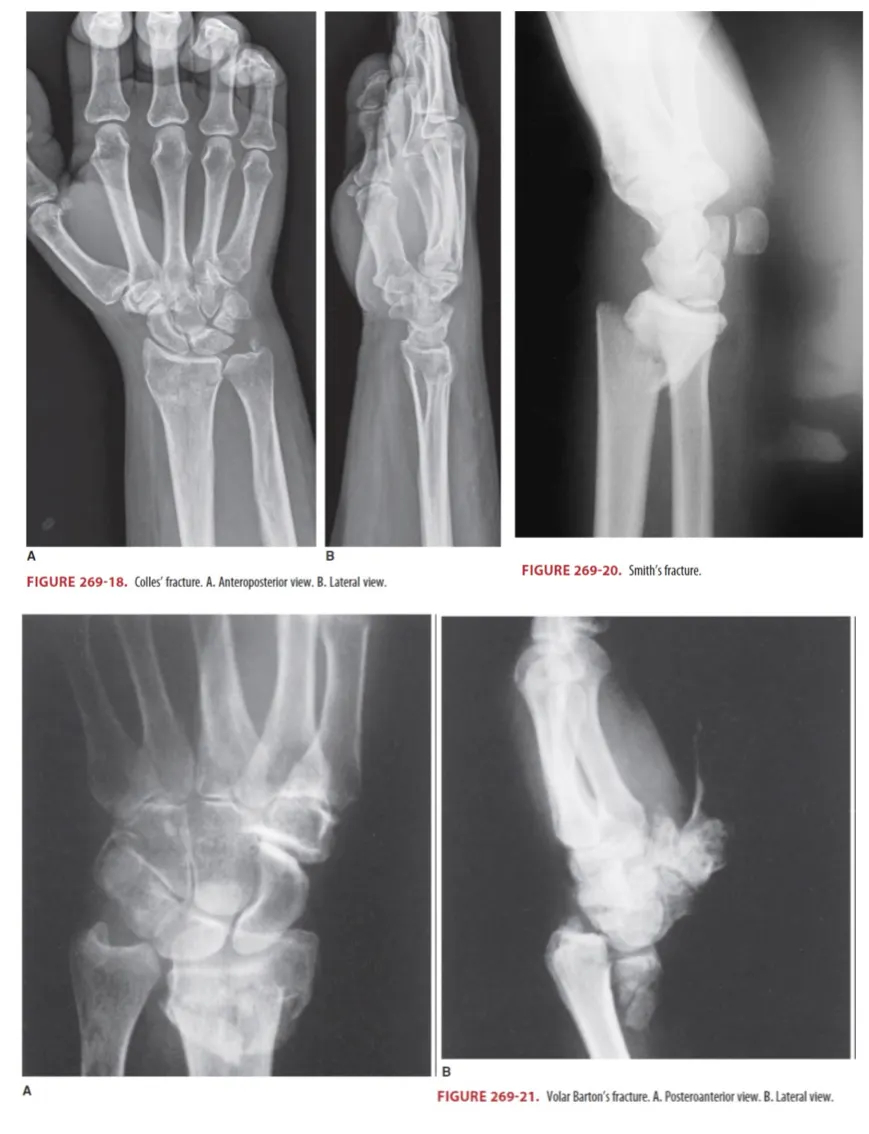

(1) 손을 밖으로 쭉 뻗은 상태에서 떨어져서 생기는 경우가 가장 흔함 (Figure 269-18)

(2) Ulnar styloid fx. 가 동반될 수 있는데 이는 TFCC 손상 동반 가능성 있음

(3) 특징적인 Wrist의 dorsiflexion, "dinner-fork" deformity 보임

(4) Dorsal angulation 및 comminution을 보는데 lateral view가 나음

(5) Unstable fx Angulation 20°,이상 intra –articular involvement comminute fx.

→ 대부분 closed reduction과 sugar tong splint로 치료될 수 있음

G2. Smith Fracture (Figure 269-20)

(1) Reverse colle’s fx. 로 불림. lateral view에서 volar angulated 되어 있음 (colle’s 와 반대)

(2) Lateral view가 angulated and displaced fx.를 가장 잘 보여준다.

(3) Garden-spade deformity

G3. Barton fracture (Figure 269-21)

(1) Distal radius의 dorsal 또는 volar rim이 골절되면서 때때로 Fx-DL이나 subluxation 을 만든다.

(2) Minimal displaced fx. 는 sugar tong splint apply & OS f/u

(3) Unstable fx.

: Radial articular surface를 50% 넘게 involve했거나, carpal subluxation이 동반되는 경우, ORIF 필요하므로 OS consult 시행함.